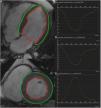

LV structure and strain analysisEnd-diastolic and end-systolic epicardial and endocardial borders from short-axis and two-, three- and four-chamber long-axis images were defined manually by a trained investigator blinded to clinical and echocardiographic parameters using cvi42® (version 5.6, Circle Cardiovascular Imaging Inc., Calgary, Canada).26 The 16-segment model was used for assessment of regional (baseline, mid-ventricular, apical) and global myocardial mechanics, including myocardial velocities and strain. Myocardial pixels were automatically tracked by the software along the cardiac cycle to generate strain measurements. Horizontal long-axis cines were tracked to derive longitudinal strain, while short-axis cines were used to derive radial and circumferential strain. Six metrics of LV morphology and function [end-diastolic volume (EDV), end-systolic volume (ESV), stroke volume (SV), LVEF, cardiac output (CO), myocardial mass (LVM)] were also recorded. Figure 2 shows the tracking of LV endocardial and epicardial borders and global LV longitudinal, circumferential, and radial strain patterns of a patient with severeAS.

Systolic function remodeling after aortic valve replacementWe found a significant decrease in mid and apical radial strain, in mid, apical, and global circumferential strain, and in GLS, six months after intervention (Table 5). Figure 3 depicts differences in GRS, GCS, GLS and LVEF measurements from baseline to six months following AVR. Even though we cannot assure statistical significance in all the following individual variations, for descriptive terms of general postoperative strain behavior considering baseline measurements, we detected variations (both increase and decrease) beyond intra-observer variability in GCS in six and 17 patients and in GLS measurements in four and 16 patients, respectively, six months after intervention. In those patients whose GLS or GCS increased, preoperative measurements were reduced. If we consider the median values in our population, six and three patients whose GCS and GLS increased beyond intra-observer variability had baseline values lower than the median, respectively. LVEF remained unchanged. RV systolic function assessed by tricuspid annular plane systolic excursion (TAPSE) and RV S wave velocity also decreased significantly and became impaired following intervention, according to the normal range reported in the literature.29

Systolic function remodeling - evolution of global radial, circumferential and longitudinal strain and left ventricular ejection fraction measurements from baseline to six months following aortic valve replacement.

LVEF: left ventricular ejection fraction; GCS: global circumferential strain; GLS: global longitudinal strain; GRS: global radial strain.

*GCS and GLS were significantly reduced after intervention.